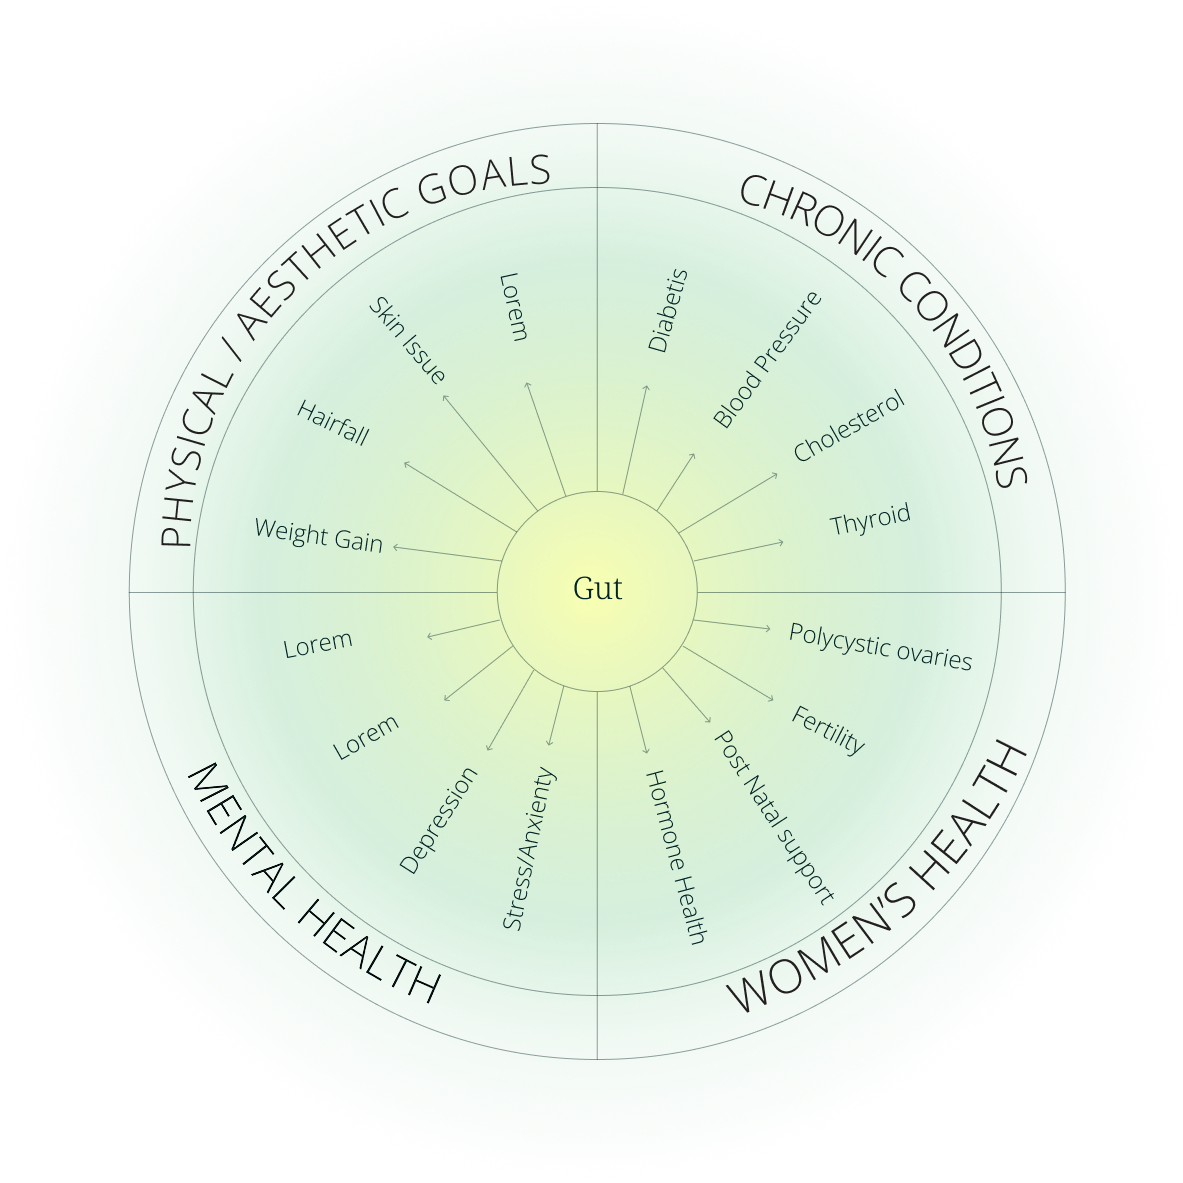

Your gut holds the key to your health. Through tongue analysis and dosha reading, we design a personalized food intelligence report suited to your unique nutrition needs, for optimal gut health.

Did you know that most diseases start in your gut? Ayurveda views the gut, or ‘Agni’ (digestive fire) as central to health. Modern science also calls the gut second brain in the human body. By making small changes in food as per Ayurvedic principles, gut health can vastly improve, leading to prevention and better management of lifestyle diseases. And in some cases, reversal as well.

Food, when matched to the unique body constitution and nutrition needs, has the power to transform health.